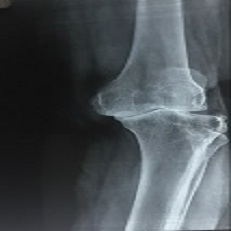

Tkr 69 Year Old

Tkr 73 Year Old